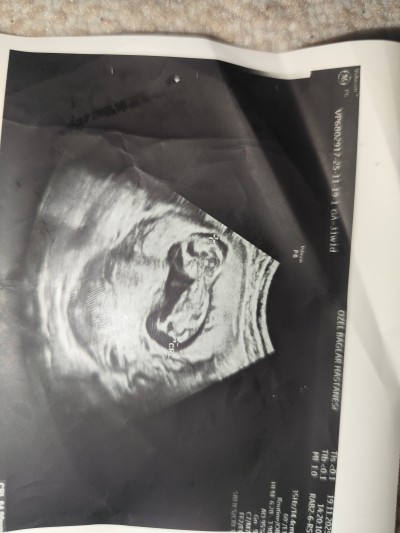

Cinsiyet tahmini yeni ultrason doktor bir defa erkek dedi sonra kız dedi

14+2 haftalık

Hayırlısı cnm sağlıklı olsun bacak arası görünmüyor sadece tahmin kız dedi ama erkek de diyince bacak arası görünüyor dedi bir hafta arayla